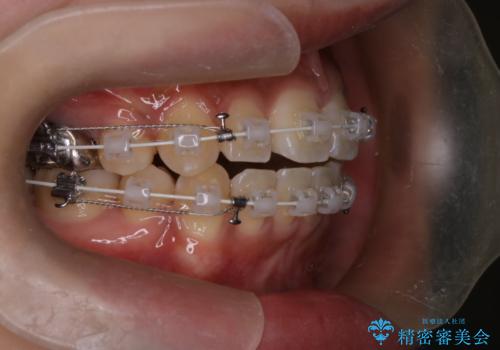

- 前歯の突出が強く、口元が前に出ている印象を改善するため、上下左右の第一小臼歯(4番)を抜歯する矯正治療を計画しました。抜歯により得られたスペースを利用して、前歯を後方へと移動させて整列します。治療には目立ちにくい透明な審美ブラケットとワイヤーを使用し、毎月1回の調整を行いながら徐々に歯を動かし、約2年で口元全体を整える計画としました。

前歯が前に出ているため口元が突出し、唇が閉じにくいなどの悩みを抱えておられました。治療にあたり上下左右の第一小臼歯を抜歯し、十分なスペースを作ることで前歯を効果的に後方へ移動させました。装置には透明で目立ちにくい審美ブラケットを採用し、治療中の審美的ストレスを軽減しました。定期的な調整を通じて無理なく確実に歯列を整え、前歯の突出感を解消。治療後は口元の印象が自然で美しく改善され、患者様には非常にご満足いただけました。